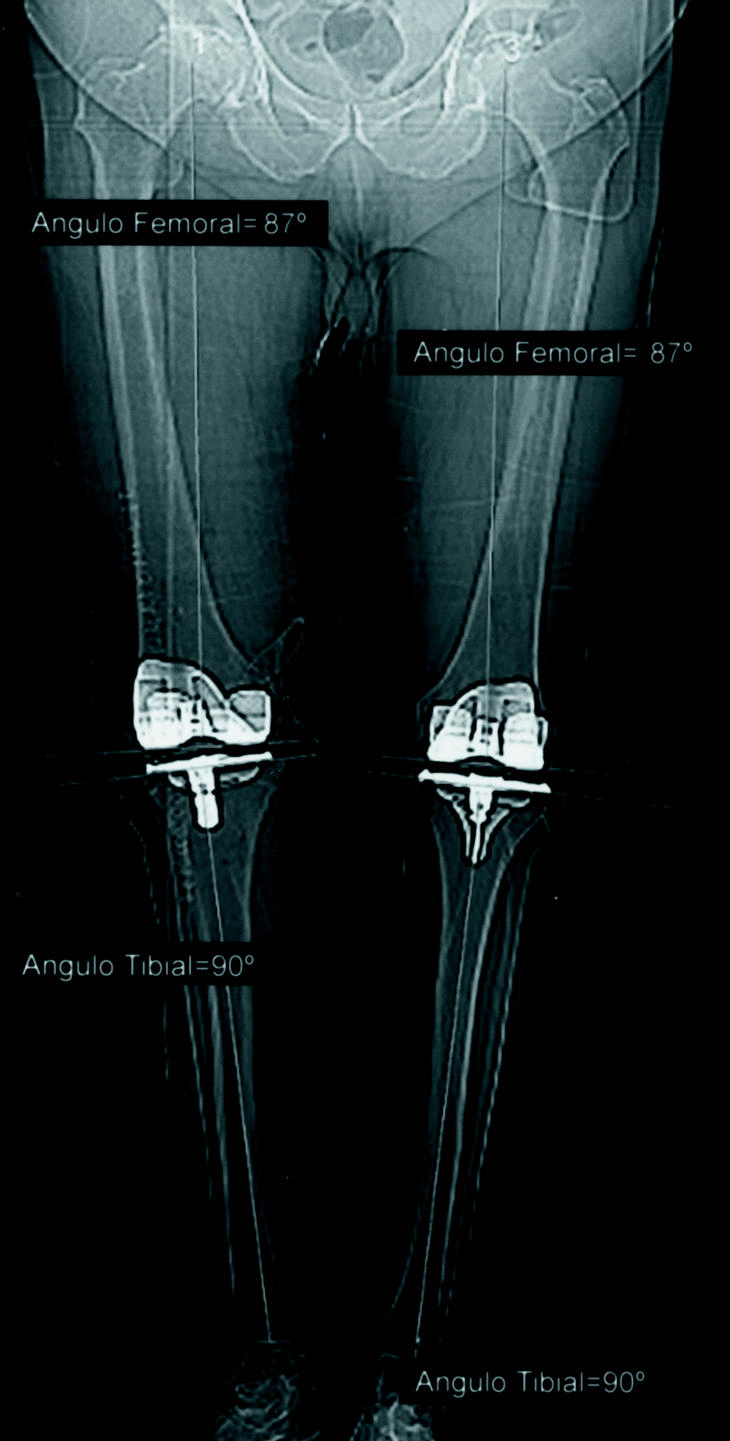

En el período postoperatorio inmediato a todos los pacientes se les realizó un estudio mediante tomografía axial computarizada (TAC) de la extremidad intervenida en carga bipodal. Para ello se utilizó un tomógrafo Siemens, modelo Somaton Volume Acces con adquisición volumétrica o secuencial y programa para topografía digital que permite exportar imágenes a través de una red interna o externa. Se obtuvieron imágenes digitales empleando la técnica llamada de surview o scanview, abarcando toda la extremidad incluyendo la cabeza femoral y el tobillo. Se utilizó un sistema de posicionamiento para la extremidad inferior con el objetivo de mantener la extremidad en rotación neutra. Se obtuvo exclusivamente la imagen anteroposterior de la extremidad, pues la lateral fue imposible de conseguir con una aceptable calidad en algunos pacientes, al tener que permanecer de pie. En cada caso se evaluaron tres angulos (fig. 5): ángulo femoral (AF) definido por el formado entre la perpendicular al eje del componente femoral y el eje mecánico del fémur, entendiendo como tal una línea que transcurre desde el centro de la cabeza femoral hasta el centro de la rodilla; angulo tibial (AT) formado por la perpendicular al eje de la plataforma tibial y por el eje anatómico de la tibia y ángulo femorotibial (AFT), formado por la unión de los ejes mecanicos del fémur y tibia. El AF y el AT muestran la calidad en la colocación de los componentes que teóricamente deben formar un ángulo de 90° con el eje mecánico del segmento óseo. El AFT es el exponente final de la colocación de la artroplastia y debe aproximarse a los 180°. El médico radiólogo que realizó la TAC y que emitió el informe con las angulaciones obtenidas no conocía a qué grupo pertenecía el paciente examinado. Los datos fueron almacenados en una base de datos (Access) y tratados estadísticamente mediante el programa SPSS.

Figura 5. Mediciones realizadas sobre TAC de la extremidad inferior .

El tiempo medio de intervención en el grupo con técnica estándar fue de 73 minutos (límites: 62-89) y en el grupo con navegación fue de 91 (límites: 83-121). En los primeros 5 casos del grupo con navegación la duración media fue de 117 minutos pero en los últimos 5 descendió a 86, evidencia de la mayor experiencia con la técnica. No se registraron complicaciones intraoperatorias ni postoperatorias inmediatas en ningún paciente, y tanto los controles de hemoglobina como la aspiración de los redones no mostraron diferencias entre los dos grupos. Para facilitar la recogida y el tratamiento estadístico de los datos se consideró la angulación en varo como negativa y en valgo como positiva. El promedio del AF postoperatorio de toda la serie fue de 91° (desviación estándar [DE]:1,52). La angulación media del AT fue de 89,9° (DE:1,84) y la del AFT de 177,6° (DE:2,39).

En el grupo sin navegador el AF osciló entre 90° y 94° con una media de 91,7° (DE:1,37); el AT se situó entre 87° y 95° con una media de 90,2° (DE:1,97) y el AFT varió de 172° a 180°, con una media de 175,9° (DE:2,06), lo que indica un ligero predominio de la desviación en varo del eje mecánico de la extremidad (tabla 1).

En el grupo con navegador el AF se situó entre 87° y 93°, con un promedio de 90,2° (DE:1,29), el AT entre 85° y 93°, con una media de 89,6° (DE:1,69) y el AFT entre 177° y 182°, con una media de 179,2° (DE:1,33).